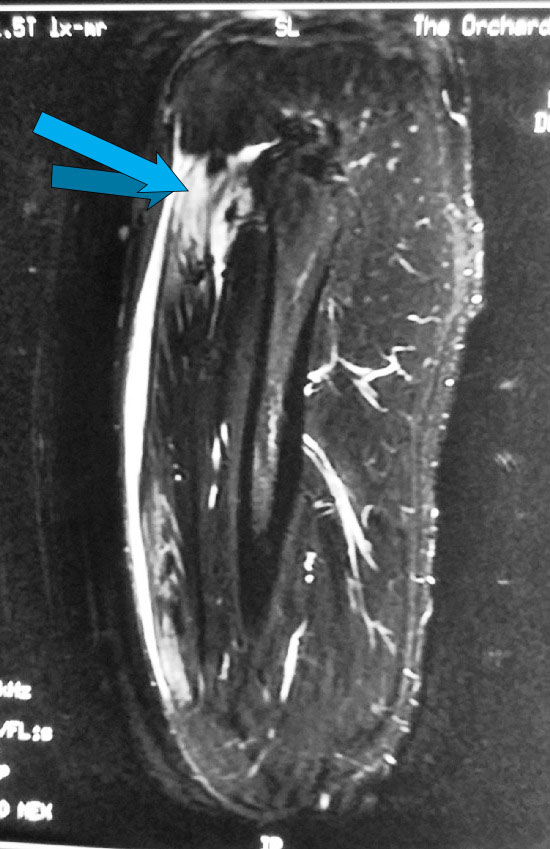

A young man experienced some minor right groin pain with sporting activities over the past 1 month. He continued to engage in sports despite the occasional right groin pain or discomfort.

He was playing football when he felt a muscle over the front of his right hip “tear”. He had sudden onset of right groin pain and was unable to continue running.

Examination showed tenderness over the front of his right hip and proximal right thigh with weakness in right hip flexion.

A clinical diagnosis of a possible right quadriceps muscle tear was made.

An MRI scan of his right thigh was ordered. The MRI confirmed a tear of the direct head of the right rectus femoris.

He was offered surgical repair of the torn rectus femoris.